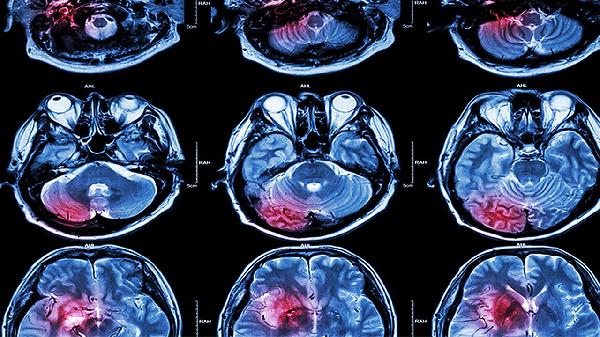

脑囊虫病的诊断主要依赖头部CT或MRI检查,可清晰显示脑内囊虫病灶的形态、数量和位置。血清学检测如酶联免疫吸附试验能辅助诊断,但需注意与其他寄生虫感染的交叉反应。脑脊液检查可能发现嗜酸性粒细胞增多或抗体阳性,但需结合其他检查结果综合判断。少数情况下,通过活检获取脑组织标本进行病理检查可明确诊断。